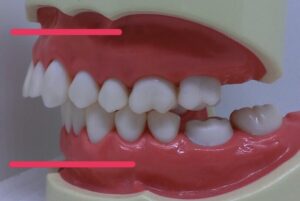

そしてまた、なんでも非抜歯がいいと思っているとこのように、

歯並びは整いますが、噛み合わせも、お顔も、木を見て森を見ず。です。

こうなってからではやり直しは、困難。